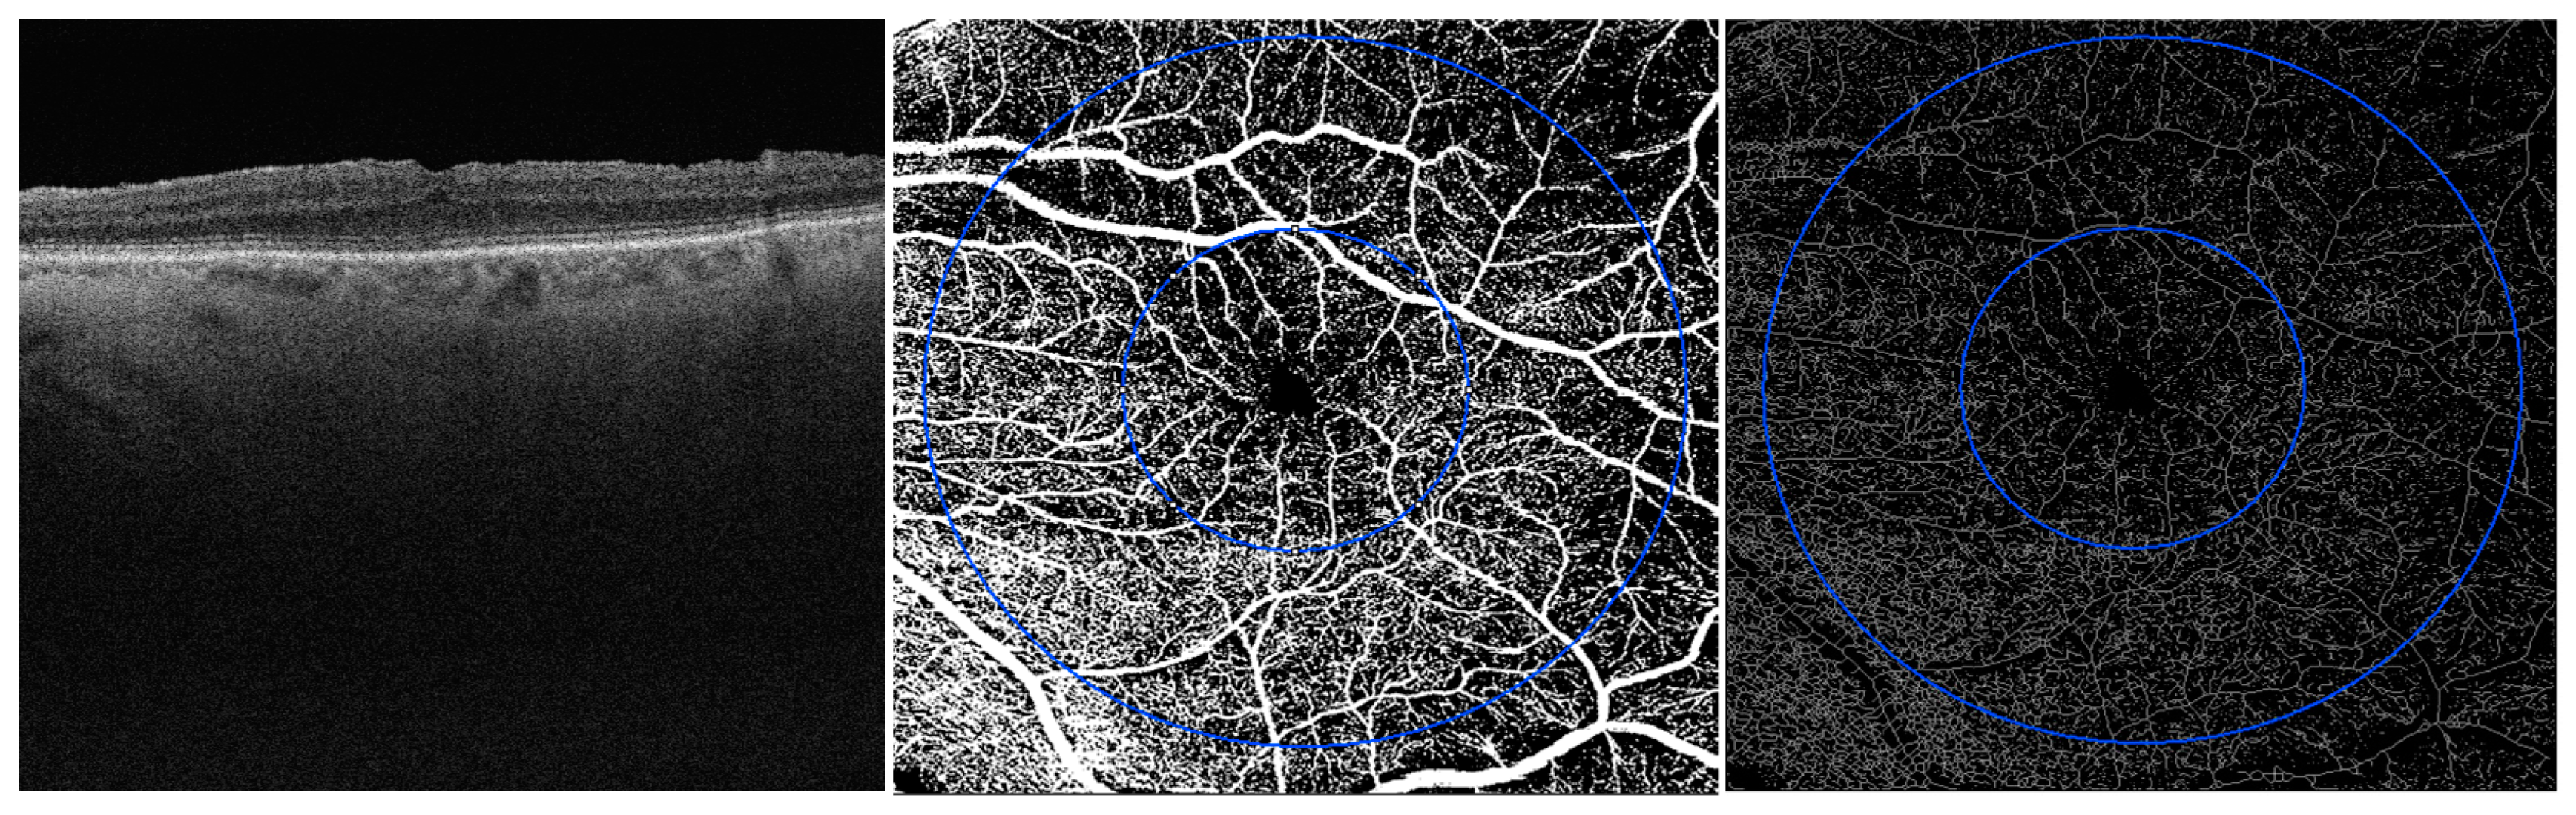

2.2. Image Acquisition

2.3. Image Processing